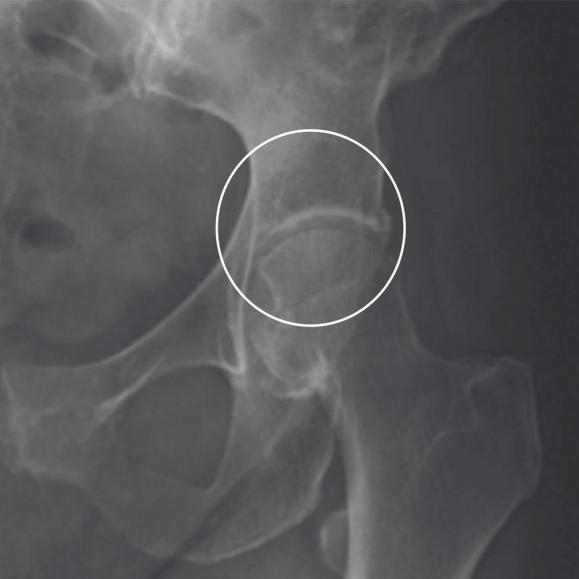

Versorgung der Hüftpfanne

Nun wird die am Beckenknochen befindliche Hüftpfanne für die Implantation vorbereitet. Mit einer speziellen Fräse formt der Herr Petersen das Implantatbett. Dort wird dann die künstliche Hüftpfanne befestigt. Das geschieht meist mit Pressdruck, selten mit Zement oder verschraubt.

Versorgung des Oberschenkels

Der Markraum des Oberschenkelknochens wird mit Spezialraspeln aufgeraut und für die Aufnahme des Hüftschafts vorbereitet. Dieser wird in den Markraum des Oberschenkelknochens eingesetzt. Darauf wiederum wird dann der Hüftkopf aufgesetzt. Hier besteht die Wahl zwischen einer Einzementierung des Schaftes mit Knochenzement oder einem Einbringen, bei dem der Knochen langsam mit dem Schaft zusammenwächst. Je nach körperlichen Voraussetzungen kann für Sie die eine oder andere Variante angeraten sein. Beraten Sie sich mit Ihrem Facharzt Herrn Carsten Petersen, um die für Sie beste Befestigungsart zu ermitteln. Ist der Schaft in den Oberschenkelknochen eingebracht, wird der Hüftkopf auf seinem Hals befestigt.